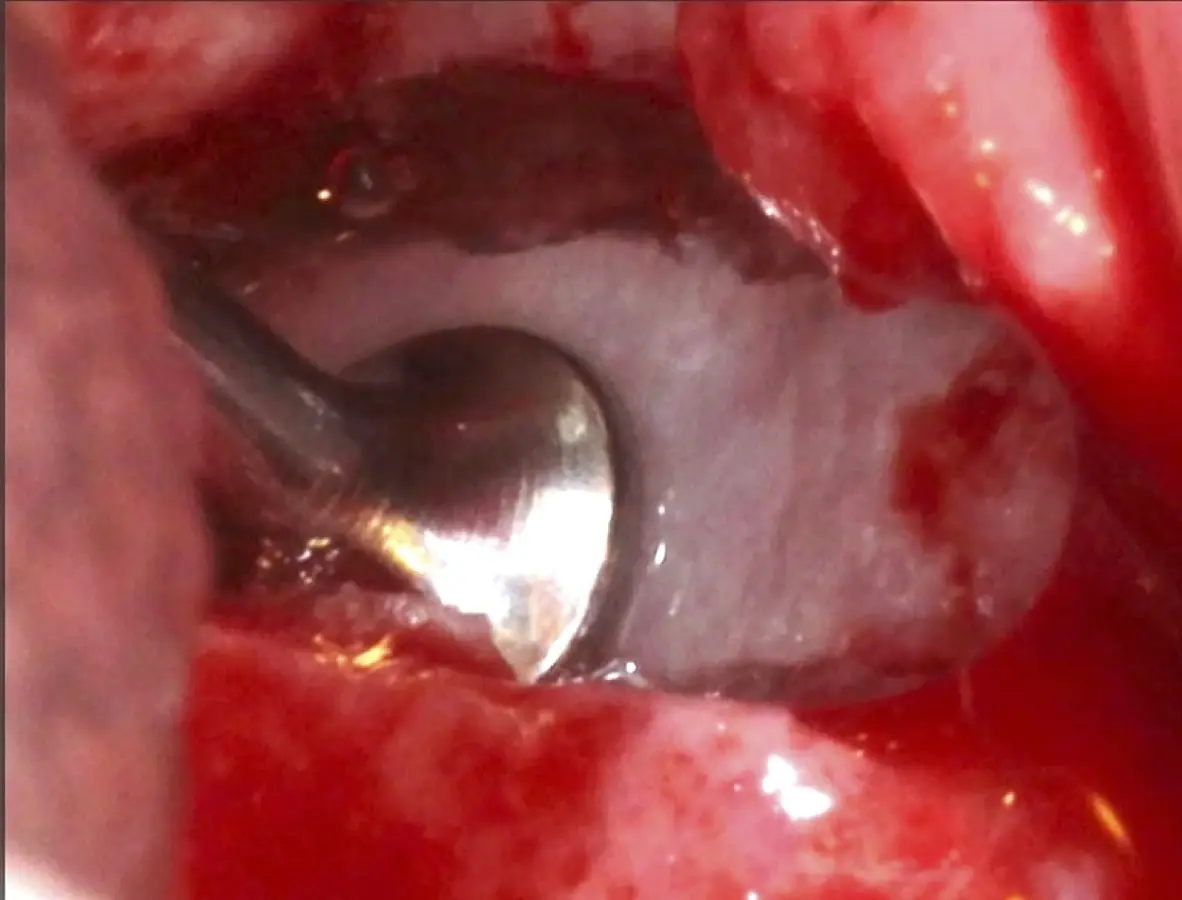

Figura 6. Técnica por retiro de la tabla ósea. Una vez retirada o fracturada la tabla ósea, se introduce el inserto de presión hidráulica entre la membrana de Schneider y los bordes de la ventana, con suaves movimientos se inicia el desprendimiento gracias al chorro de agua expulsado a través del inserto (Figura 7).

Inserto de presión hidráulica iniciando el desprendimiento de la membrana de Schneider (a, b ).

Figura 7. Inserto de presión hidráulica iniciando el desprendimiento de la membrana de Schneider (a, b ).